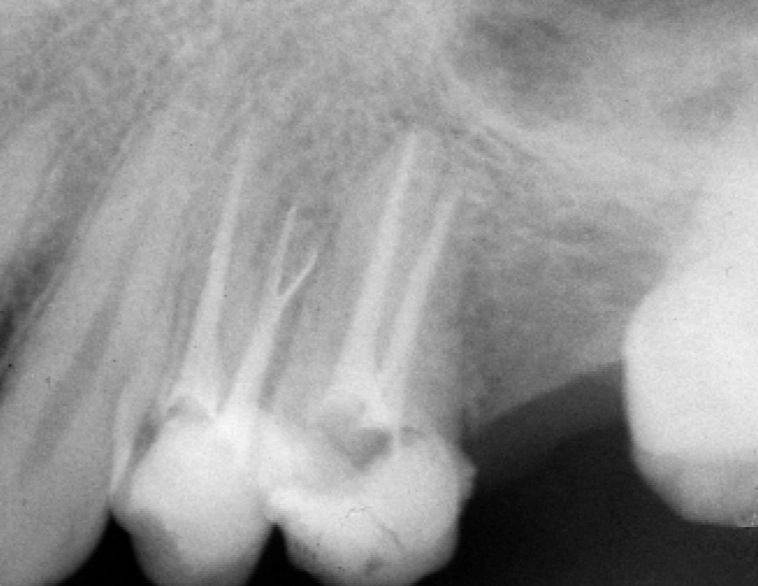

The biggest headache with premolar root canals is their root structure. While a front tooth typically has one simple root canal, a premolar can be a surprise package.

| Upper First Premolar | 2 roots, 2 canals (very common) | Often has two separate roots. Missing one canal is a leading cause of failed treatment. |

| Upper Second Premolar | 1 root, but often 2 canals inside it | The single root frequently splits into two canals (a "web" shape), easy to miss. |

| Lower Premolars | 1 root, 1 canal (usually) | Generally simpler, but the canal can be curved or narrow, requiring fine instruments. |

This variability is why some premolar root canals feel straightforward, while others require the precision of a specialist (an endodontist). I once had a patient whose upper first premolar had three separate canals—a configuration you won't find in any textbook but happens more than people think. If a dentist isn't using a dental microscope and only takes one standard X-ray, they might completely miss an extra canal, leaving infected tissue behind. That tooth will hurt again in six months, guaranteed.

First, good imaging is non-negotiable. A periapical X-ray shows the length of the roots. For complex cases, a 3D cone beam CT scan might be used. This gives a detailed map, crucial for navigating those tricky, multi-canal premolars. Your dentist will also administer local anesthesia. The idea that root canals are painfully done is a complete myth—if you feel sharp pain, speak up. More anesthetic can be given. You should only feel pressure.